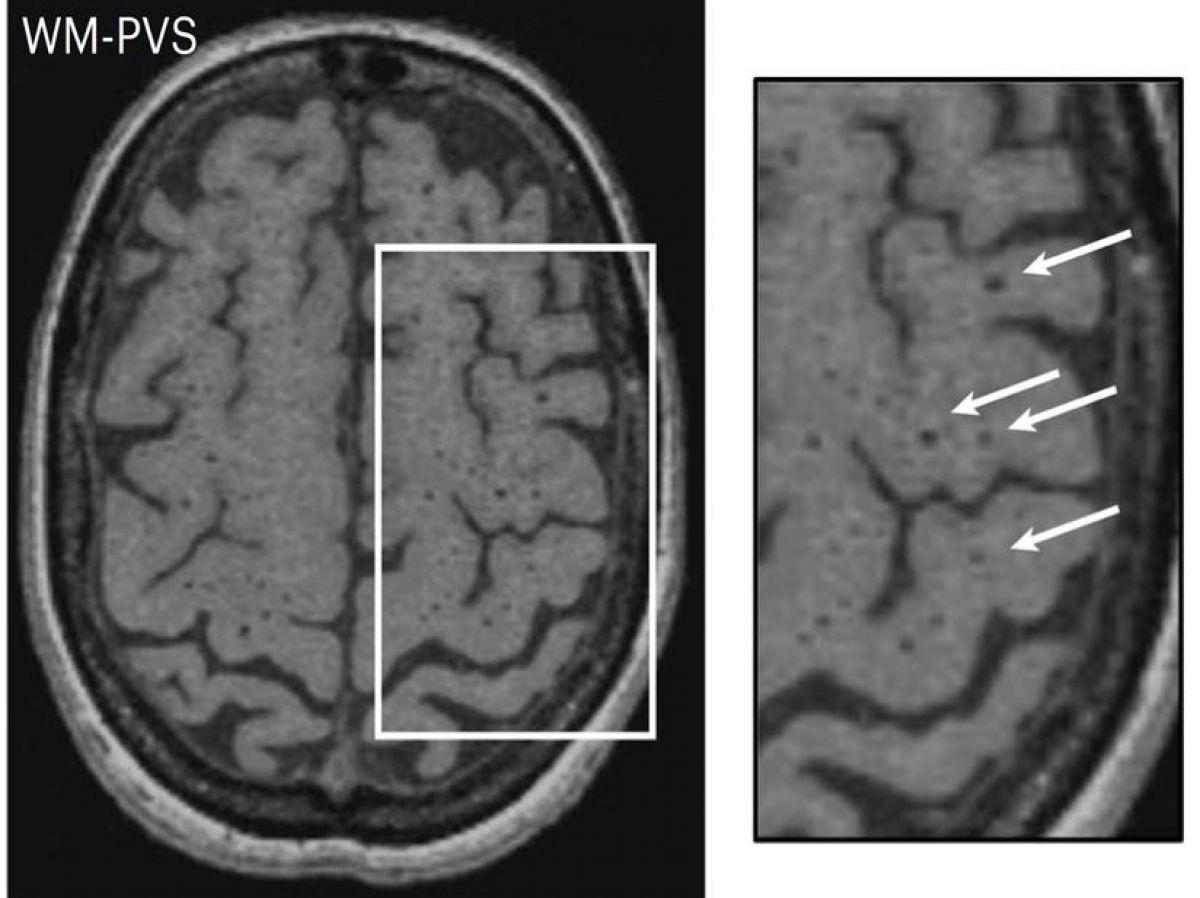

Espaces périvasculaires

Les chercheurs se sont ainsi focalisés sur les gènes impliqués dans l’apparition d’espaces périvasculaire (EPV). Les EPV sont des espaces physiologiques entourant les parois des petits vaisseaux sanguins dans le cerveau et permettant notamment l’élimination des déchets du cerveau. Détectables à l’IRM, ils constituent un des marqueurs IRM de la maladie des petites artères cérébrales permettant de la diagnostiquer avec d’autres altérations telles que les hypersignaux de la substance blanche, les infarctus lacunaires ou les microsaignements.